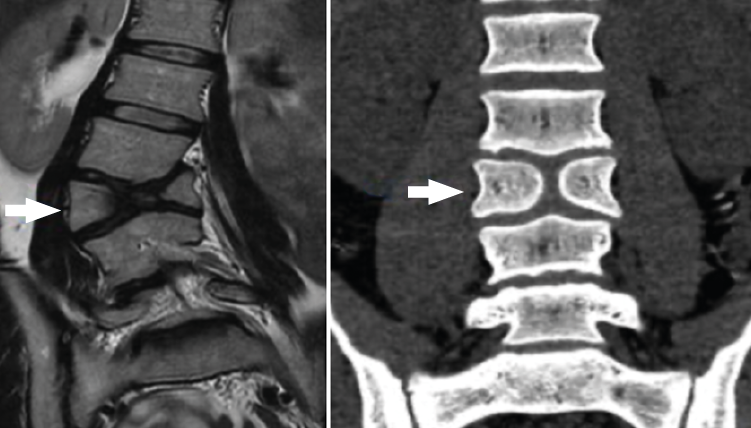

Ofrece una excelente definición de las estructuras blandas (tanto intra- como extrarraquídeas). Permite una buena visualización del saco dural y su contenido, sin la necesidad de tener que inyectar contraste intratecal, además de permitir la detección de patologías intramedulares. Es, por tanto, la técnica diagnóstica de elección ante la sospecha de una patología específica de partes blandas, discos intervertebrales, ligamentos y saco neural, así como en la evaluación de una posible afectación tumoral, infecciosa o metabólica del raquis vertebral lumbar (Figura 13).

Figura 13. Hernia de disco extruida.

Las principales indicaciones para el empleo de esta técnica en el estudio de la patología dolorosa lumbar serían:

- La sospecha clínica de hernia discal: de elección, especialmente en pacientes jóvenes sin signos de espondilosis ni estenosis del canal vertebral; debería reservarse para pacientes candidatos a un tratamiento quirúrgico o aquellos que, con síntomas o signos de radiculopatía, no responden adecuadamente al tratamiento conservador pautado durante un periodo variable de 4 a 6 semanas.